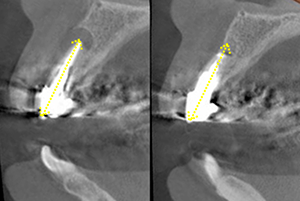

This is a surgical procedure that includes extraction. One such procedure is called " apicoectomy." (Figures 20 and 21)

The brief description of this procedure is that the contaminated root apex is cut away.

First, the gum around the root apex is detached to expose the root apex. Then,after removing about 2 mm of the tip, the bacteria around the tip are scraped off with scraper.

...the roots become shorter and less supportive of the teeth.

In other words, as the roots that support the tooth become shorter, the tooth is more likely to shake, and if it becomes infected with periodontal disease, even slightly, it will have to be extracted.

It is also common for the tips of the roots to naturally resorb because they are not in their original natural shape.